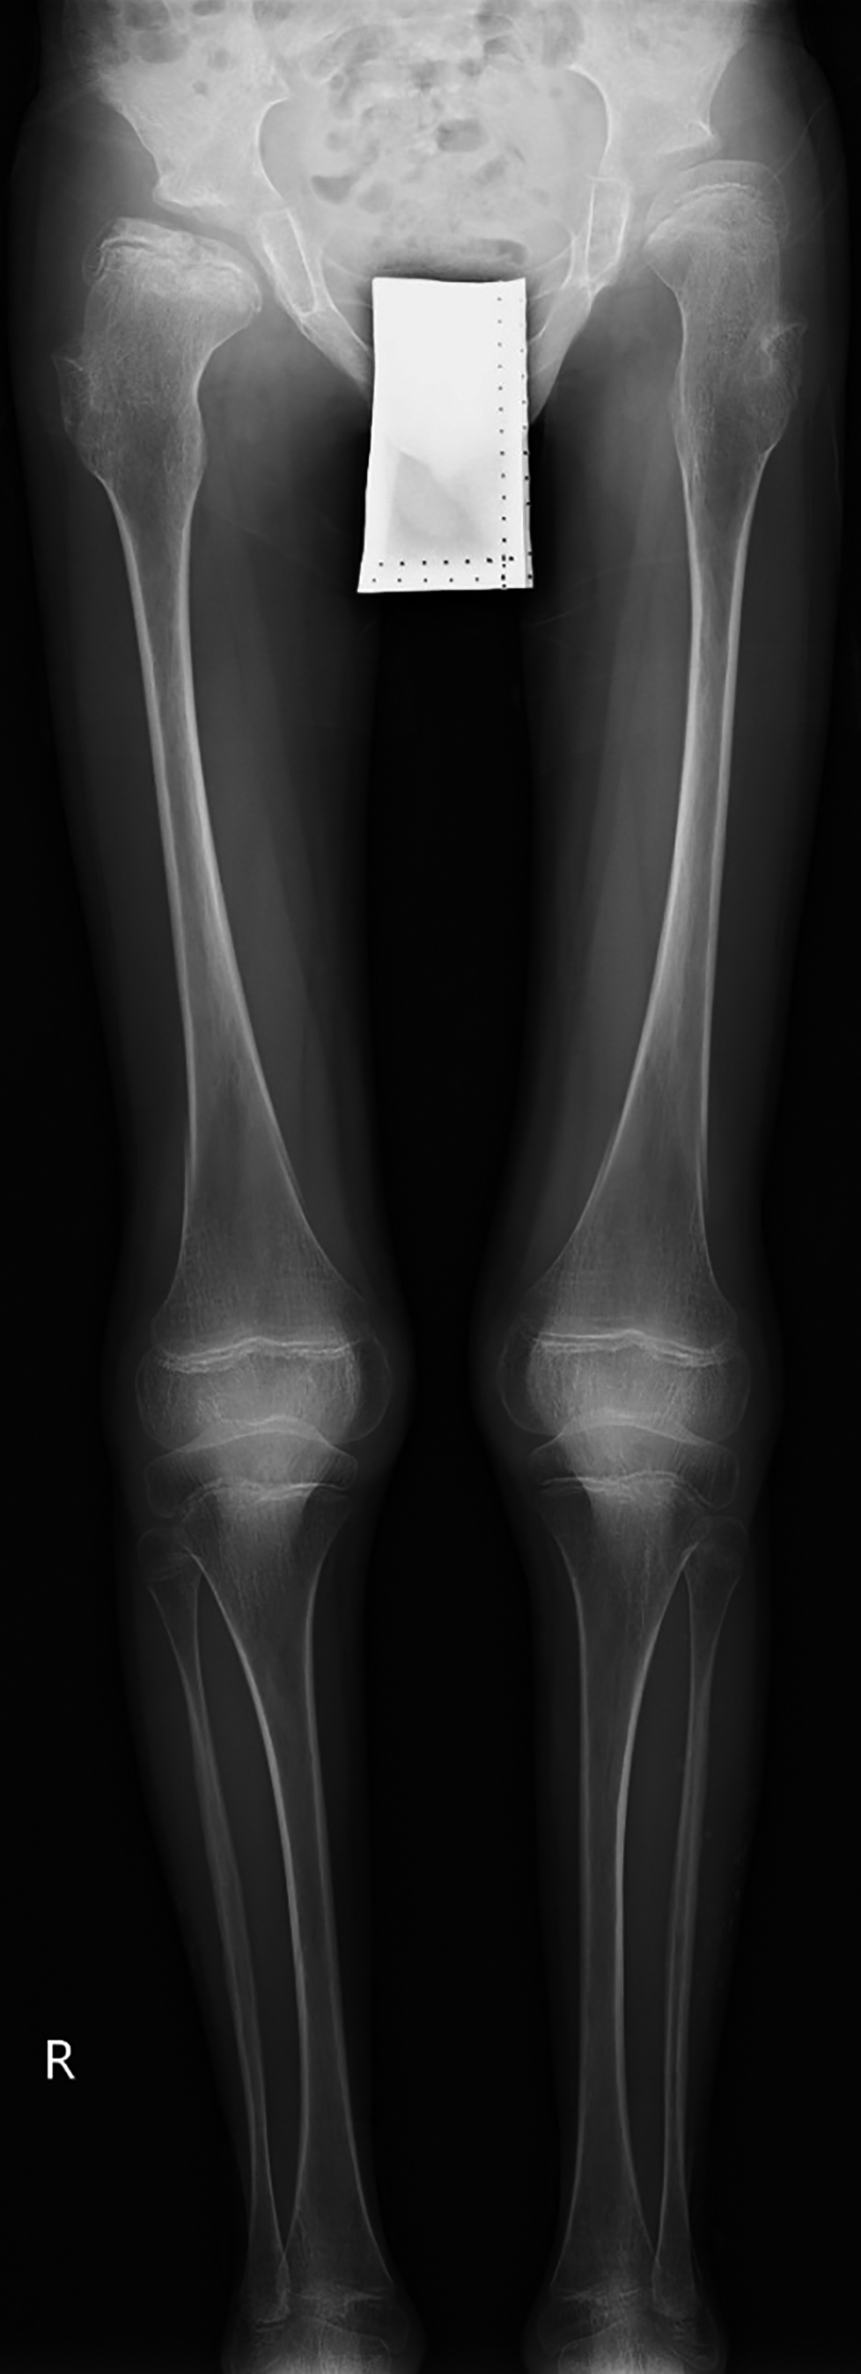

Рисунок 4. Пациент №3, 7 лет 5 мес., с синдромом Хатчинсона-Гилфорда.

Рентгенография таза с захватом нижних конечностей на протяжении. Выраженные изменения формы и структуры эпифизов и метафизов бедренных костей; болезнь Легга-Кальве-Пертеса 3 ст.; экструзия головки правой бедренной кости; coxa valga с двух сторон; врожденный подвывих левого бедра.

При объективном осмотре ортопеда и рентгенологическом обследовании выявлены асептический некроз головки правой бедренной кости (болезни Легга-Кальве-Пертеса) 3 ст; экструзия головки правой бедренной кости; coxa valga с двух сторон; врожденный подвывих левого бедра (рис. 4). Также имели место множественные контрактуры локтевых, лучезапястных; тазобедренных, коленных, голеностопных суставов, сочетающиеся с деформациями контрактурами суставов пальцев кистей и стоп (табл. 2).

При осмотре в возрасте 9 лет 3 месяцев отмечено прогрессирующее снижение росто-весовых показателей, сохранение специфического фенотипа, ортопедические проявления без существенной динамики. При рентгенографии кистей рук выявлено незначительное опережение костного возраста, по результатам денситометрии — остеопороз (табл. 2).